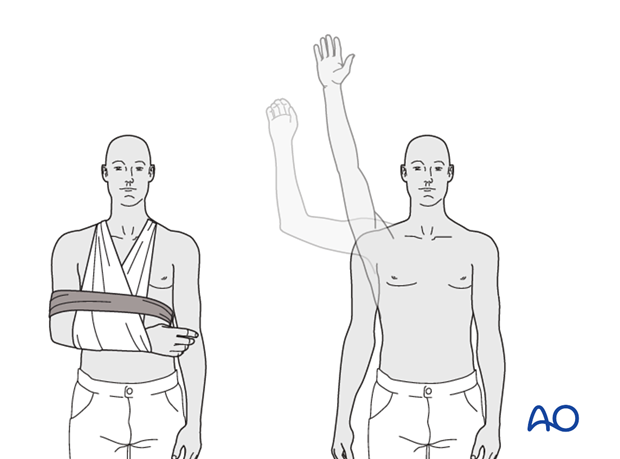

Phase I: Immobilization and Early Protected Motion (Weeks 0-6)

* Immobilization: Arm in a sling (e.g., shoulder immobilizer) for 4-6 weeks. The duration depends on the surgeon's assessment of fixation stability and bone quality. The sling should be removed for exercises and personal hygiene.

* Exercises (Daily):

* Elbow, Wrist, Hand AROM: Encourage frequent active range of motion of the elbow, wrist, and hand to prevent stiffness and promote circulation.

* Pendulum Exercises: Gentle, gravity-assisted swings of the arm while leaning forward, to initiate glenohumeral motion without active muscle contraction of the shoulder.

* Passive External Rotation: Typically limited to 0-30 degrees initially, using the contralateral hand or a stick. Avoid stretching into painful ranges.

* Passive Forward Flexion/Abduction: Supported by a therapist or with the contralateral hand, within pain-free limits, usually not exceeding 90 degrees in the initial weeks.

* Scapular Mobilization: Gentle scapular retraction and protraction exercises.

* Restrictions:

* NO active shoulder motion.

* NO lifting.

* NO weight-bearing through the affected arm.

* NO sudden movements or reaching overhead/behind the back.